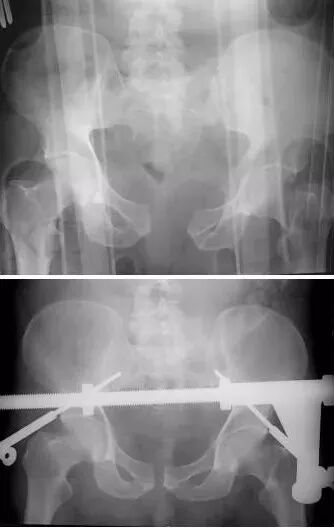

2)骨盆骨折

30min,三个决定:

• 开放性骨折,立即止血;

• 骨盆制动(10-15min);

• 观察10-15min,血流动力不稳定,能否手术?

图片

血流动力学稳定,在7天内手术?